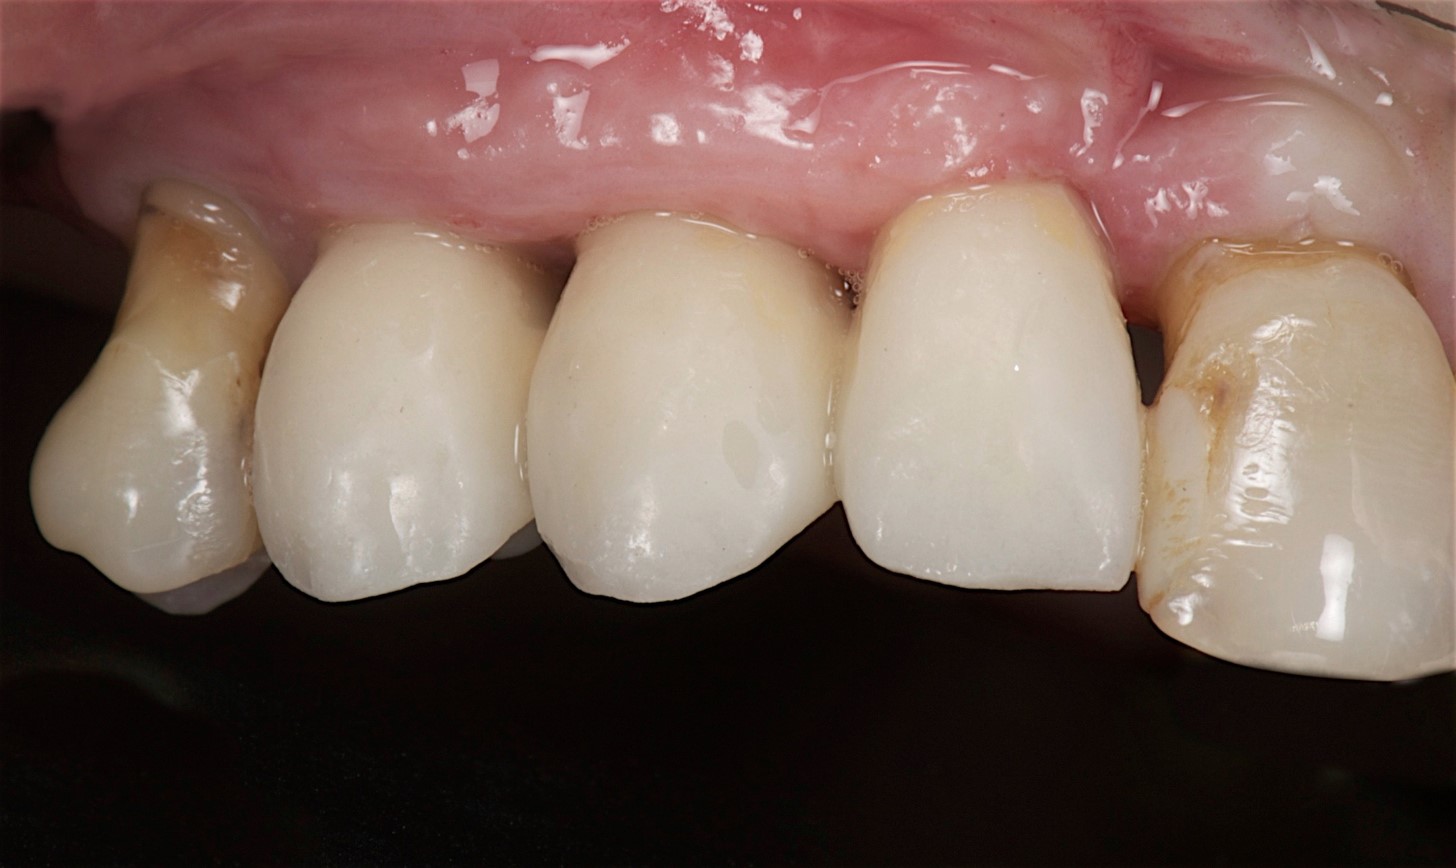

Fig 10. After 15 days of healing, a nice volume of keratinized mucosa and tissue was present.

Figure 10

Fig 11. The prosthodontist created provisional restorations that would help condition the soft tissue for creating an esthetic emergence profile.

Figure 11

Fig 12. View of the definitive implant-supported restorations.

Figure 12